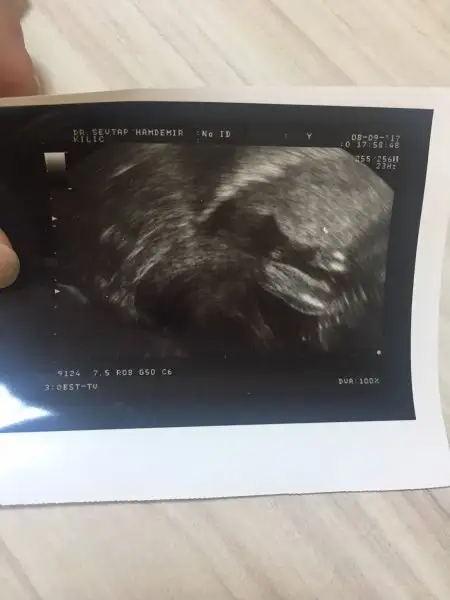

kızlar alttan baktıgı ultrason bu neredesınde yazıyor bu rahım agzı uzunlugu bı bakar mısınız

kızlar benim ölçüme bakabilir misin rica etsem ben anlamadım nerede yazan o ölçü bilemedim